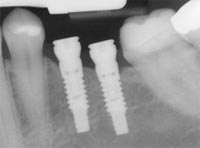

An implant is a new tooth made of steel and porcelain that looks just like your natural tooth or better! Your implant is composed of two parts that mimic a tooth's root and crown. The implant's "root" is a titanium steel rod placed into the jaw bone to act as a root. Once the rod is in place, a porcelain crown is attached to replace the top part of your tooth.